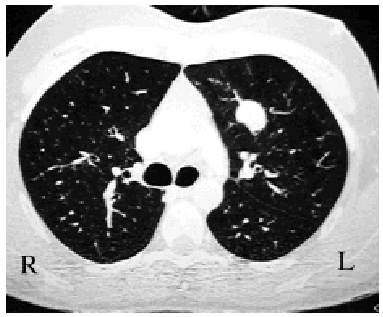

Macroscopically, they appear well defined but nonencapsulated, hard, and yellowish-white or grayish when sectioned. Most are found in the pulmonary parenchyma (Figure 1), but they can be endobronchial,2 causing obstruction. Fewer than 5% show invasion of the mediastinum or the thoracic wall.1

Figure 1. Chest CT scan showing a well-defined in traparenchymal pulmonary lesion. The postoperative diagnosis was inflammatory pseudotumor.